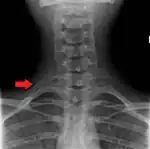

A C7 rib on the right

Variation

Variations in the number of ribs occur. About 1 in 200–500 people have an additional cervical rib, and there is a female predominance.[13] Intrathoracic supernumerary ribs are extremely rare.[14] The rib remnant of the 7th cervical vertebra on one or both sides is occasionally replaced by a free extra rib called a cervical rib, which can mechanically interfere with the nerves (brachial plexus) going to the arm.